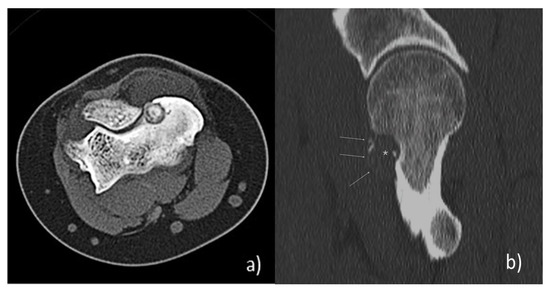

- Poullain, F.; Mattei, J.C.; Rochwerger, A.; Bouvier, C.; Chagnaud, C.; Champsaur, P.; Le Corroller, T. Percutaneous cryoablation of osteoblastoma in the proximal femur. Skelet. Radiol. 2020, 49, 1467–1471. [Google Scholar] [CrossRef]